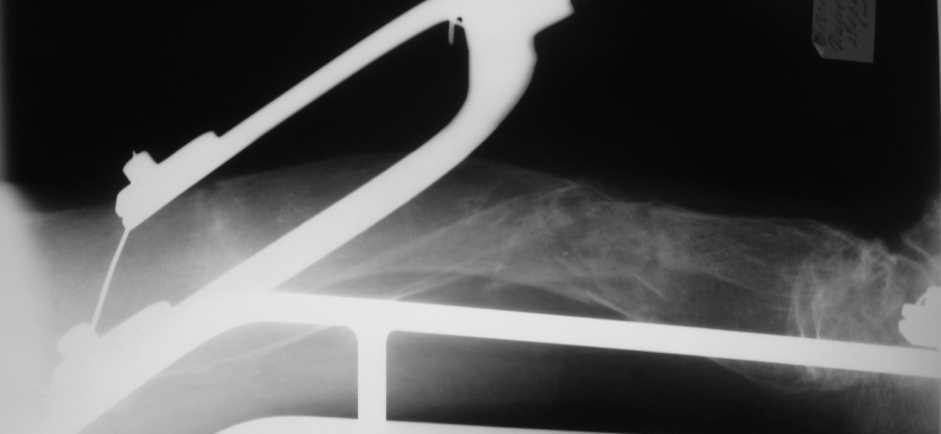

Но даже при малоинвазивной методике лечения применимой для даной больной существуют следующие проблемы: выраженный остеопороз, тонкий кортикал, очень широкий канал.

Контрольные рентгенограммы прилагаю.

Проблема в том, что в сагитальной плоскости угол голеней =30 градусам. Ширина канала 30.

Будет ли остеосинтез стержнем стабильный?